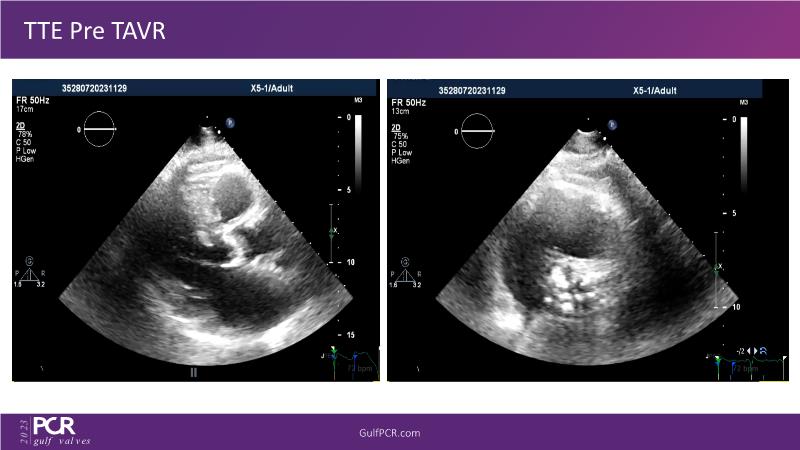

Essentials of lifetime management of TAVR patients using novel Myval THV

Join this GulfPCR-GIM 2023 session to explore the Myval next-generation THV technology, uncovering its unique features, procedural advantages, and clinical benefits, from extensive patient data. Learn also about the CorAlign technique that ensures precise commissural and coronary alignment while preserving coronary access, and gain insights into the precise sizing, positioning, and deployment techniques for the Myval THV.